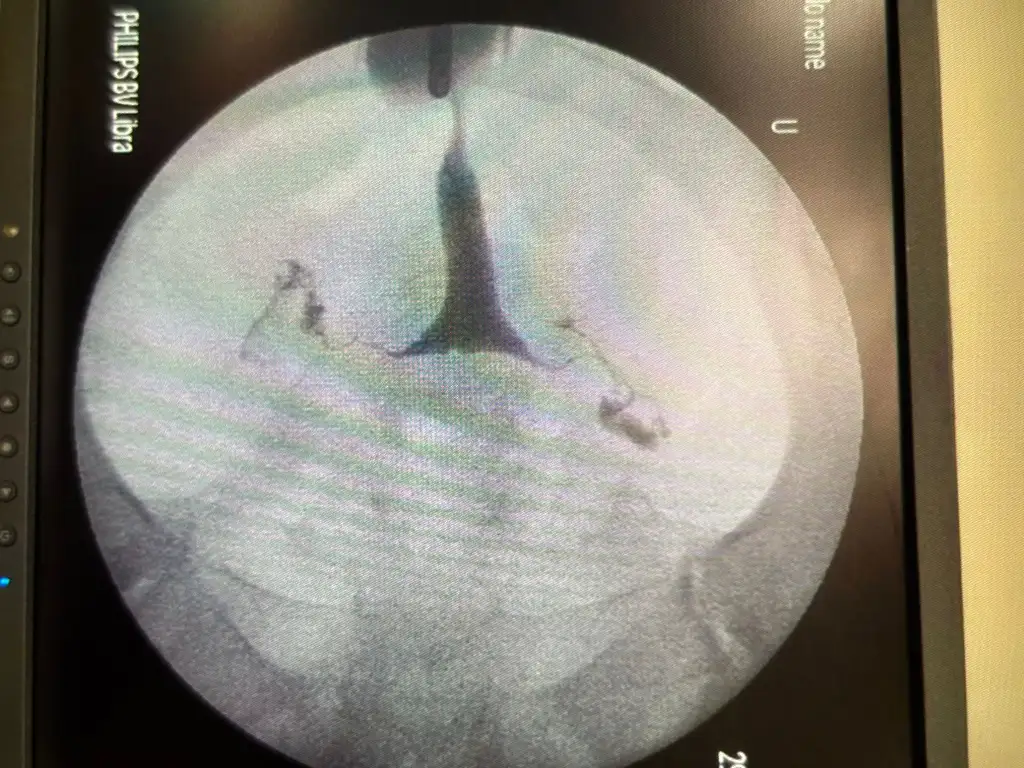

Cnm pcosda yumurtalar adet olacak kadar büyüyo fakat döllenecek kadar büyümüyo. Yani ovülasyon baksan bile yumurtan döllenecek kadar büyümediği için pek başarılı olmayabilirsin. Onun için klomen ve femera yazıo doktor. Yumurta büyütmek için. Bende de pcos var klomen ve femera kullanıyorum bu ay 2 yumurtam büyüdü doktorun dediği günleri değerlendirdik. O şeklde yani doktor kontrollü ilaç kullanman gerek. Ovülasyon testinde pik görsen bile yumurta yeteri kadar büyümediği için döllenme olmaz.kızlar selam, 14 aylık evliyim 21 yaşındayım. kendimi bildim bileli düzensiz adet olurum yani yılda kendiliğimden bir iki kere geri kalanı söktürücüyle oluyorum. Evlendiğimden beri hiç korumuyorum çocuk istiyorum fakat henüz olmadı. hormonlarıma bakıldı amh bakıldı bir sıkıntı göremediler ultrasonla alttan muayenelerde polikistik görünümü var ama hormonlar desteklemiyor tam polikistik diyemeyiz diyorlar anlamıyorum bende. dün hsg çekildim tüplerim de açıkmış bir sıkıntı yokmuş filmin fotoğrafını da yükleyeceğim buraya. Sizce ovulasyon testi kullansam başarılı olur muyum? yoksa pkos olduğu için ovulasyon işe yaramaz mı?

Bana kalsa hsg cektirmissin biraz daha kendim dene.. bende dün çektirdim ve kendim denemeyi düşünüyorum hatta doktorların çoğu hsgden sonra 3-6 ay arasında gebelik elde edildiğini söylüyor.. üç ay ben kendim ovulasyon testleriyle denemeyi düşünüyorum bende 15 aydır gebelik istiyorum ve doktorum banada ultrason da pcos görüntüsü var küçük yumurtaların var ama bu skıntı değil hormonların gayet güzel demişti düzenli adetimide oluyorum ve bir kez kimyasal gebelik yaşadım 6 ay önce.. çok kafaya takmamaya bak sağlıklı beslen her gün yürüyüş yap inşallah hayırlısıyla olur.. ben dikkat etmeye başladımkızlar selam, 14 aylık evliyim 21 yaşındayım. kendimi bildim bileli düzensiz adet olurum yani yılda kendiliğimden bir iki kere geri kalanı söktürücüyle oluyorum. Evlendiğimden beri hiç korumuyorum çocuk istiyorum fakat henüz olmadı. hormonlarıma bakıldı amh bakıldı bir sıkıntı göremediler ultrasonla alttan muayenelerde polikistik görünümü var ama hormonlar desteklemiyor tam polikistik diyemeyiz diyorlar anlamıyorum bende. dün hsg çekildim tüplerim de açıkmış bir sıkıntı yokmuş filmin fotoğrafını da yükleyeceğim buraya. Sizce ovulasyon testi kullansam başarılı olur muyum? yoksa pkos olduğu için ovulasyon işe yaramaz mı?